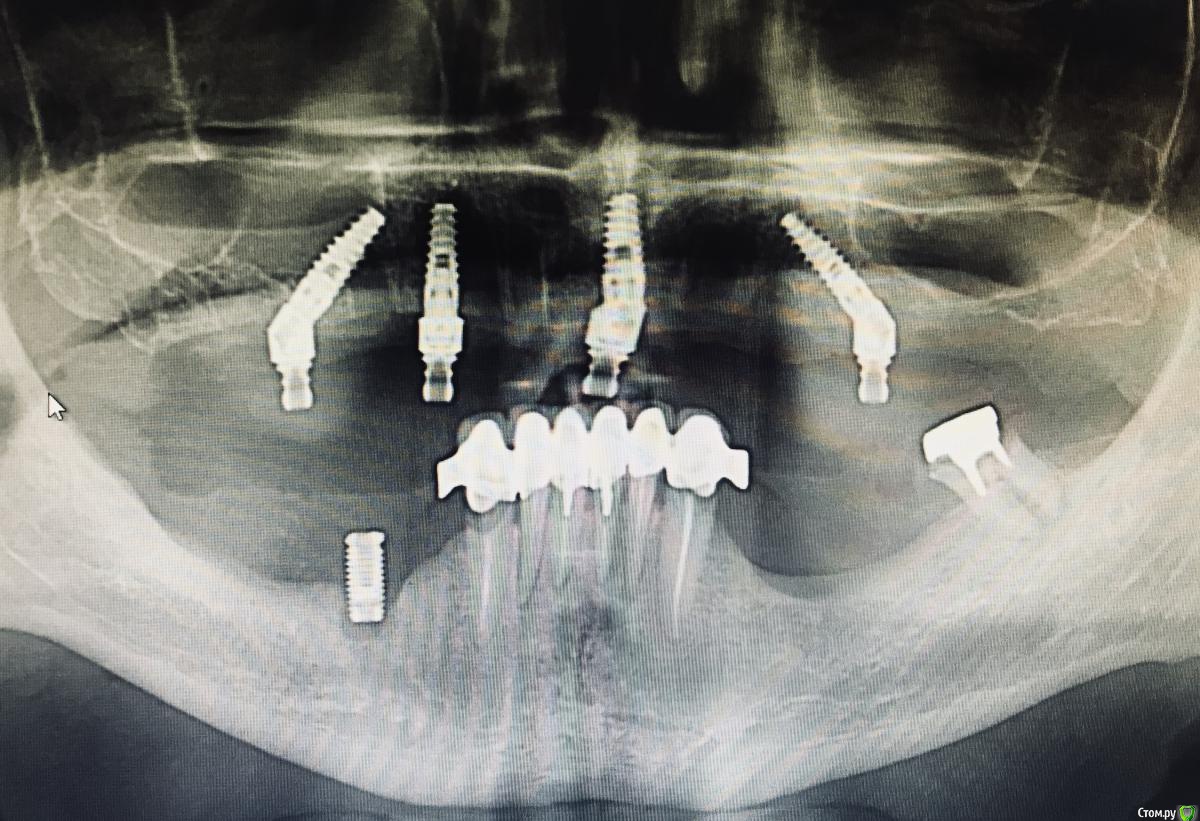

DoctorT Опубликовано 12 июля, 2018 Поделиться Опубликовано 12 июля, 2018 Вот так определяю) 1 4 Ссылка на комментарий

DoctorT Опубликовано 14 июля, 2018 Поделиться Опубликовано 14 июля, 2018 (изменено) сняли силиконом, подрезали по межальвеолярной высоте, по типу восковых валиков и скрепили узы корегиром?) валик из жесткого силикона, в полости рта жесткой опорой для них служит трансферы для закрытой ложки. Главное, чтобы валик внутренней поверхностью не касался слизистой и опирался лишь на трансферы. Все слепки и валики сразу после установки имплантантов, протезы на следующий день. Изменено 14 июля, 2018 пользователем DoctorT 3 Ссылка на комментарий

DoctorT Опубликовано 14 июля, 2018 Поделиться Опубликовано 14 июля, 2018 (изменено) От и до ровно сутки. Н/ч на очереди. Изменено 14 июля, 2018 пользователем DoctorT Ссылка на комментарий